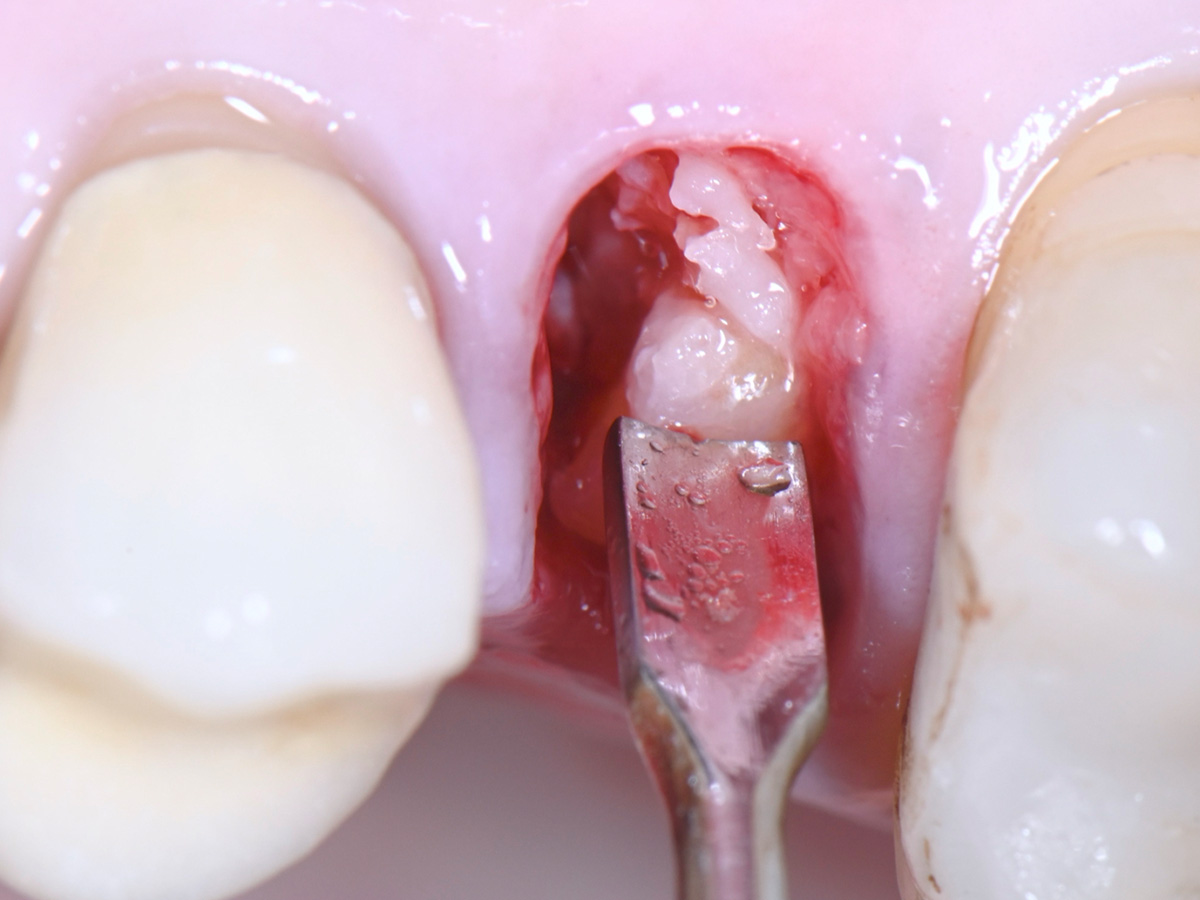

Abbildung 6

Entfernung des entzündlichen Gewebes aus der Extraktionsalveole